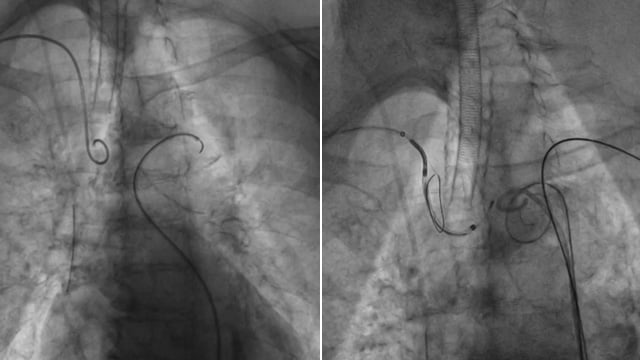

Valve in valve in small degenerative surgical bioprosthesis - LIVE case

A 74-year-old female with a permanent pacemaker and preserved LV function presented with a symptomatic degenerative surgical valve (SJ Epic 21) implanted in 2016.

Patient underwent implantation of an Evolut FX 26 mm under general anesthesia with cerebral embolic protection and TEE guidance. A surgical valve fracture...